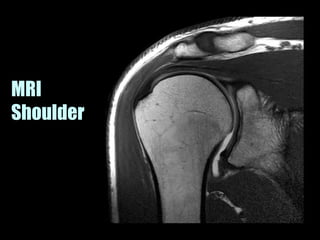

This document provides an overview of normal musculoskeletal imaging. It discusses basic x-ray concepts and densities. It then reviews normal anatomy as seen on x-rays of the skull, spine, pelvis, chest, and extremities. Key anatomical structures are labeled on example x-rays for the shoulder, hip, knee, and foot. Quizzes are included to test recognition of anatomical structures and patient age based on x-rays.